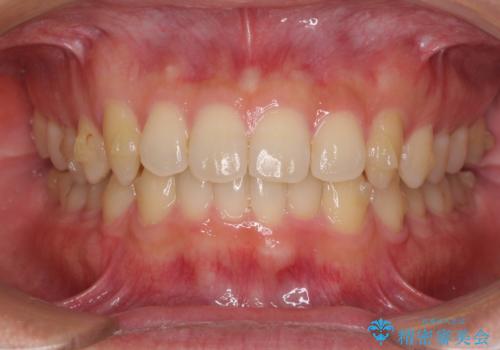

前歯の咬み合わせとデコボコを解消 インビザラインによる矯正治療

- 上下前歯のデコボコと深い咬み合わせを気にして来院された患者様です。

インビザラインによる上下歯列の拡大と、IPR(歯と歯の間を削る)にるスペースの獲得により、前歯のデコボコとディープバイトを改善することとしました。

もう少し下の前歯を整えたかったのですが、患者様の治療を早く終了させたいという希望により、細かい叢生を残しての終了となりました。